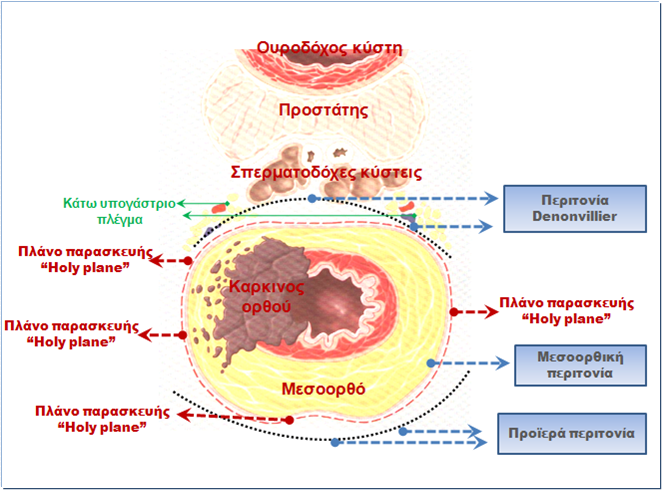

Η ολική μεσοορθική εκτομή είναι ουσιαστικής ογκολογικής σημασίας και αποτελεί απαραίτητο τμήμα όλων των χειρουργικών τεχνικών που εφαρμόζονται για τη ριζική χειρουργική αντιμετώπιση των καρκίνων του μέσου και του κατώτερου ορθού, δηλαδή αυτών που εντοπίζονται σε απόσταση έως και 12 cm από το πρωκτικό άνοιγμα. Περιλαμβάνει την πλήρη αφαίρεση του λιπώδους περιβλήματος του ορθού, το οποίο περιέχει λεμφαγγειακό ιστό, λεμφαδένες και τυχόν εναποθέσεις καρκινικών κυττάρων που μεταναστεύουν στο λιπώδη ιστό μετά από νεοπλασματική διήθηση του μυϊκού χιτώνα του ορθού. Η ολική αφαίρεση του μεσοορθού λαμβάνει χώρα περιμετρικά, οπισθίως, πλαγίως και προσθίως διατηρώντας ανέπαφη την ιδίως μεσοορθική περιτονία, η οποία αποτελεί το σπλαγχνικό πέταλο της πυελικής περιτονίας και περιβάλει πλήρως το μεσοορθικό λίπος. Ο ανάγγειος περι-μεσοορθικός χώρος, ο οποίος, χειρουργικά, παρασκευάζεται οξέως, και ποτέ αμβλέως, αντιστοιχεί:

- Κατά το οπίσθιο τμήμα του στον προϊερό χώρο, δηλαδή στο διάστημα μεταξύ της προϊεράς περιτονίας (τοιχωματικό πέταλο της πυελικής περιτονίας) και της ιδίως μεσοοορθικής περιτονίας (σπλαγχνικό πέταλο της πυελικής περιτονίας), οι οποίες συντήκονται οπισθίως του κατώτερου ορθού στην ενιαία στερεά περιτονία Waldayers.

- Στα πλάγια στο χώρο ανάμεσα στη σπλαγχνική μεσοορθική περιτονία και τις περιτονίες των πλαγίων μυών της πυέλου. Στον πλάγιο μεσοορθικό ιστό, ο οποίος παλαιότερα αναφερόταν ως «πλάγιοι σύνδεσμοι» εισέρχονται αυτόνομα νεύρα του ορθού και οι συχνά υποτροφικά, αν όχι ανύπαρκτα μέσα αιμορροϊδικά αγγεία.

- Προσθίως αντιστοιχεί στη σύντηξη της πρόσθιας μοίρας του σπλαγχνικής πυελικής περιτονίας με την οπισθοκυστική περιτονία, που φέρεται ως περιτονία Denonvilliers.

Η ολική μεσοορθική εκτομή αποτελεί αναπόσπαστο κομμάτι κάθε σωστής ογκολογικά επέμβασης για καρκίνο του ορθού. Φαίνονται διαγραμματικά οι ανατομικές σχέσεις με σημαντικές δομές της περιοχής